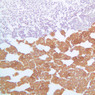

Examine slide B-56 (H&E [2.5x, 10x, 20x, 40x-labeled] [10x, 20x, 40x-labeled] [20x, 40x] [10x, 20x, 40x-labeled] [10x, 20x, 40x]). The connective tissue capsule of each parathyroid gland is continuous with that of the thyroid gland. It extends into the substance of the gland, dividing it into poorly defined lobules. Fat cells may separate the groups of cells and increase with age. Note the rich capillary network. The parenchyma is composed of two types of cells: (1) Principal or chief cells and (2) oxyphil cells. The polygonal chief cell is by far the more numerous cell type. Its nucleus is centrally located and has a vesicular chromatin pattern with a prominent nucleolus and its cytoplasm stains rather lightly. Oxyphil cells, which are less regular in shape and considerably larger than chief cells, are scattered singly or in small clusters. Their nuclei are smaller and more condensed than those of the chief cells and, owing to a very rich complement of mitochondria, their cytoplasm is distinctly acidophilic.